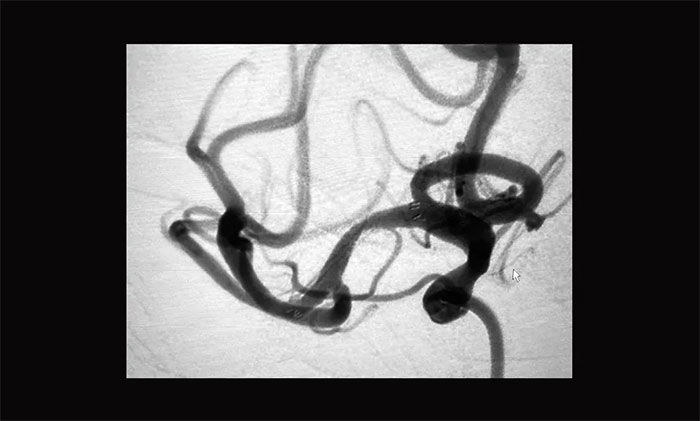

支架导管到位右侧大脑中动脉M2段上干,随后经微导管顺利置入支架,造影见支架贴壁良好,完全覆盖狭窄段,狭窄改善明显,支架内血流通畅,远端血流良好,手术顺利完成。

▲ 术后DSA影像:右侧大脑中动脉血流恢复

术后,患者意识清楚,语言流利,左上肢无力感消失,四肢活动自如,由于经桡动脉造影,术后即可下床行走,无需制动24小时。复查颅脑CT未见出血及新发梗死,目前患者正在康复中。